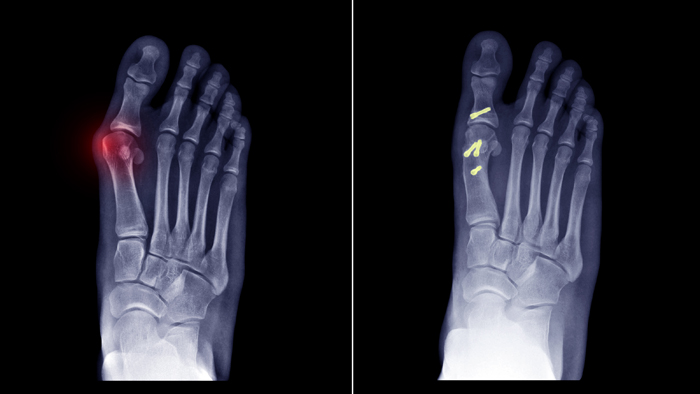

Correction of deformity is a surgical procedure to modify and adjust misaligned bones for proper functioning. The process is called corrective osteotomy, under which a bone is stabilized through internal or external fixation. In other words, it’s a surgery that cuts and reshapes deformed bones.

- Osteotomy

In the case of osteotomy, a surgeon removes the damaged part of the bone and stabilizes it with screws, plates or rods. - Spinopelvic fixation

- The surgeon starts with cutting across the bone.

- The surgeon will then align the bone in its actual place.

- He/she will secure the bone with internal fixators like nails, plates, etc. till it is healed.